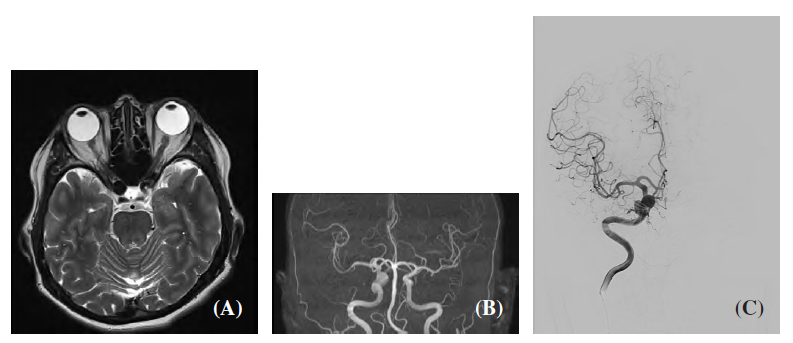

V rámci společného projektu proof-of-concept byl analyzován případ pacientky s aneurysmatem na jedné z hlavních mozkových tepen. Výpočetní dynamika tekutin (CFD) zde sloužila jako podpůrný nástroj, který v realistickém 3D modelu cév vytvořeném z angiografických dat umožnil kvantifikovat parametry, jako jsou smykové napětí, oscilace toku nebo doba setrvání krve. Na základě výpočtů bylo možné porovnat vybrané hemodynamické charakteristiky před a po zákroku.

CT snímky aneurysmatu u sledované pacientky